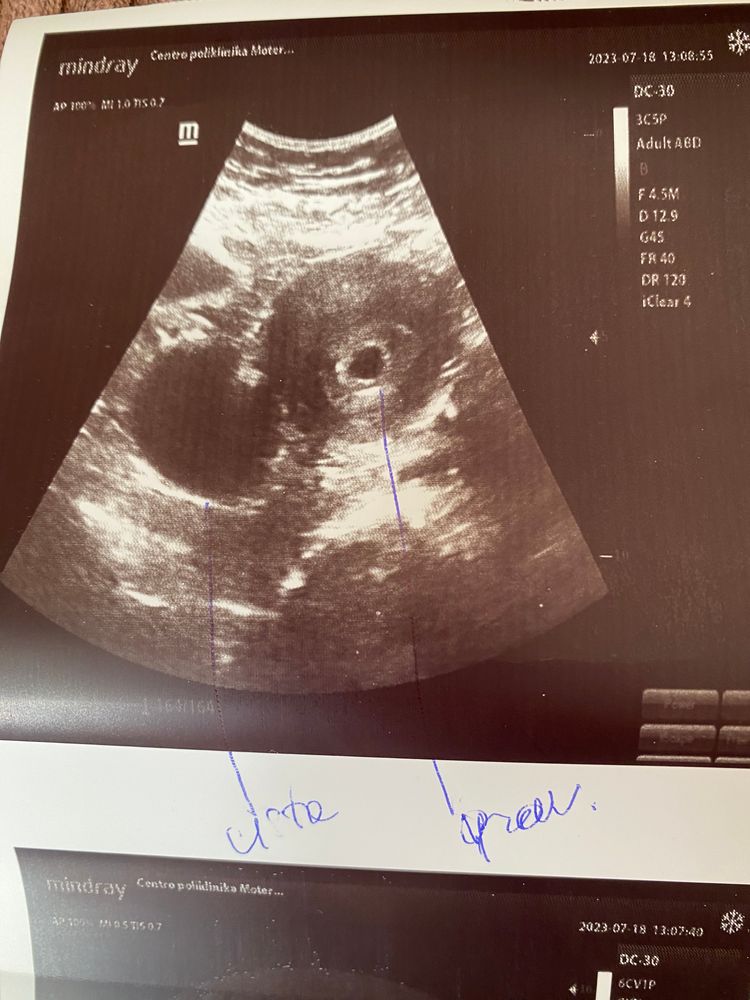

По узи прставили срок 6.2 недели.. яйцо плодное 2.15 см!.. а в середине пусто.. сказала еще недельку подождать и что то делать..

Может есть кто знает как позначены размеры плодного яйца на фото с узи?.. Узистка сказала срок 4-5 недель и нету ничего кроме плодного яйца( все нормально, оно появится позже если все норм, я это все знаю), больше ничего не скпзала

Размер 2.15